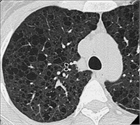

1. LAMを疑うべき特徴的な臨床像と高分解能胸部CT画像所見を契機とした診断アルゴリズムが示されている。しかし、約20%の症例では非典型的画像所見を示すことがあり注意が必要である。